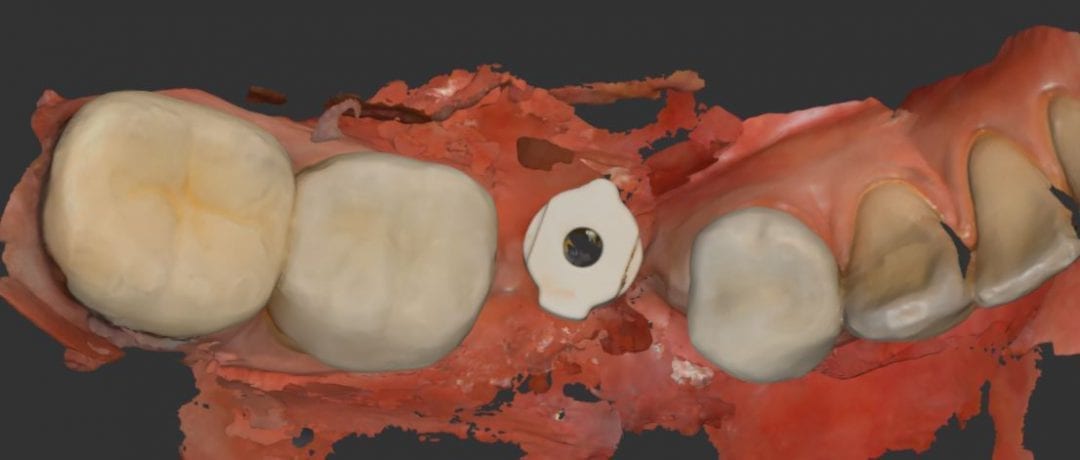

Another example of how well the i500 from Medit can scan with a deep focal length. This is impossible to do with any other IOS system on the market. Don’t […]